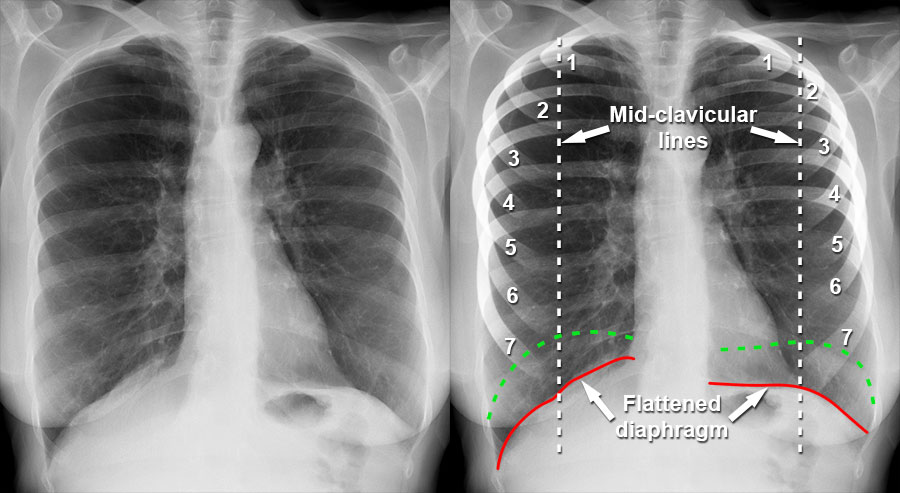

Since the beginning of the year 1980 and at the beginning of the first days of the Iran-Iraq war, which lasted 8 years, and because of the lack of resources and the many sad situations that began to appear clearly on the Iraqi people, and after entering Iraq into a war with the neighboring country Kuwait, it fell ill in 1990 and Iraq invaded it and the occurrence of the popular uprising in 1991 and the siege began on Iraq by the United Nations, and since then, there have been clear signs of Iraqis going to smoke, clearly and extensively, as an alternative and to alleviate the pain and suffering experienced by these people. Therefore, one of the most important and violent diseases caused by smoking appeared in Iraq..which is COPD<br /><br />COPD is a common disease that mainly affects middle-aged or elderly smokers. many people don't know they have it<br /><br />1. Introduction<br /> Since the beginning of the year 1980 and at the beginning of the first days of the Iran-Iraq war, which lasted 8 years, and because of the lack of resources and the many sad situations that began to appear clearly on the Iraqi people, and after entering Iraq into a war with the neighboring country Kuwait, it fell ill in 1990 and Iraq invaded it and the occurrence of the popular uprising in 1991 and the siege began on Iraq by the United Nations, and since then, there have been clear signs of Iraqis going to smoke, clearly and extensively, as an alternative and to alleviate the pain and suffering experienced by these people. Therefore, one of the most important and violent diseases caused by smoking appeared in Iraq..which is COPD<br />It is estimated that Iraqis consume daily cigarettes worth $1.8 million, the bulk of which goes to importing cigarettes through smuggling from Iraq’s neighboring countries, at a time when the percentage of smokers in the country is estimated at 35% of both sexes, which means that the total number of smokers is About 14 million Iraqis out of a total of 42 million.<br /> 2. patient and methods<br />Smoking in Iraq is a widespread and culturally acceptable behavior in Iraqi society. Since 2003, there has been a lot of pressure from the government to enforce strict smoking rules. In 2009 it became illegal to smoke in or around public buildings, although the ban remains unpopular with the Iraqi public and its enforcement is patchy.<br /><br />A 2015 study by health advocates stated that about 55 Iraqis die every day from tobacco-related illnesses. Compared to 10 people dying daily in Iraq due to terrorism and violence..<br />Smoking in Iraq is a widespread and culturally acceptable behavior in Iraqi society. Since 2003, there has been a lot of pressure from the government to enforce strict smoking rules. In 2009 it became illegal to smoke in or around public buildings, although the ban remains unpopular with the Iraqi public and its enforcement is patchy.<br /><br />A 2015 study by health advocates stated that about 55 Iraqis die every day from tobacco-related illnesses. Compared to 10 people dying daily in Iraq due to terrorism and violence.<br />Tobacco advertising is in theory prohibited, and it is illegal to smoke in public, but these laws are not systematically enforced. A 2015 survey by the World Health Organization found that there were multiple billboards throughout the capital Baghdad promoting tobacco as well as in hospitals and schools. The same survey found that 13% of Iraqi districts do not have smoking cessation programs aimed at helping smokers quit.<br /><br />Government taxes on cigarettes are high but relatively low at less than 50%; Most packages sell for less than a dollar<br />3. Results <br />In many cases that suffer from COPD we found that the progression of the disease leads to a complete collapse of the respiratory system, which necessitates a full intervention and the admission of the patient to the intensive care ward because of the patient's need for artificial respiration, and for this we had to train the workers intensively on how to Dealing with such patients also training staff in the intensive care department who are graduates of anesthesia and intensive care techniques on how to secure the airway and blood supply and how to ensure the complete function-ing of the respiratory system<br />4-discussion<br /> The results of the article include that in the future we must open several halls and specialized centers for the treat-ment of patients COPD especially the opening of special centers in intensive care in all hospitals and from all levels first, secondary and tertiary, and lounges must be provided such as ... because an increase in the number of Iraqi smokers may lead to In the coming days, there will be a significant increase in the number of patients suffering from COPD<br /><br />بواسطة : م. كرار نادر عبد عون